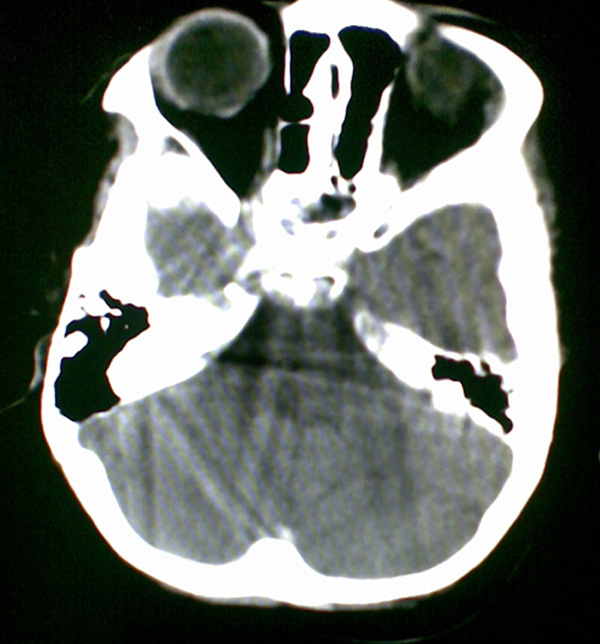

男4岁,反复抽搐多年,今早再次大抽搐,伴昏迷

1)右侧大脑半球大面积脑梗塞。2)双侧额叶脑软化灶。3)脑萎缩。

建议:必要时行dsa检查排除烟雾病可能。